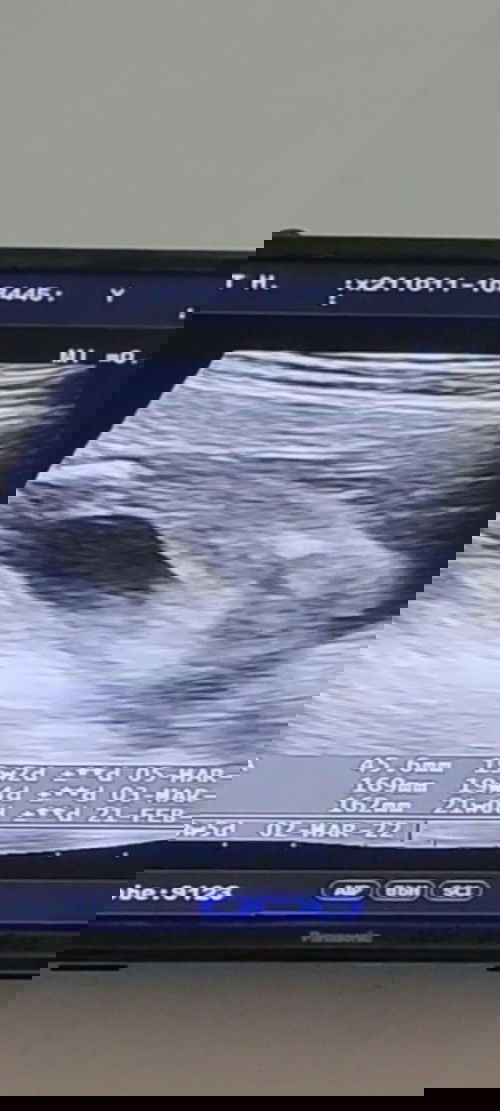

แม่แม่ว่าผู้หญิงหรือผู้ชายคะไปอัลตร้าซาวด์แล้วคุณหมอไม่แน่ใจว่าผู้หญิงหรือผู้ชาย

แล้วแบบนี้ได้เพศไหนคะ

ชายคะ